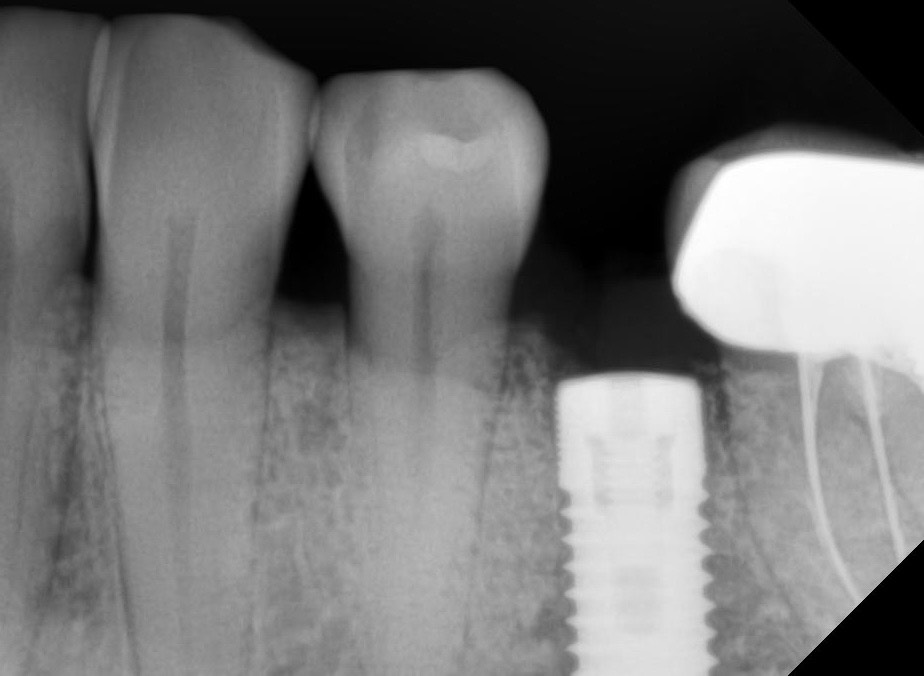

Панорама до удаления и установки импланта. Прицельные сделали вчера до депульпирования 34.

Зуб 3.5, а не 4.6, понять по снимку немецкий или нет сложно (желательно знать конкретную марку), по снимкам ничего криминального нет, но если причина болей в импланте то снимки ещё недели две ничего и не покажут.

Решение о депульпировании принимается скорее на основании клинического осмотра, снимки тут имеют вспомогательное значение

судя по предоставленным снимкам явных причин депульпировать 3.4 зуб я не вижу